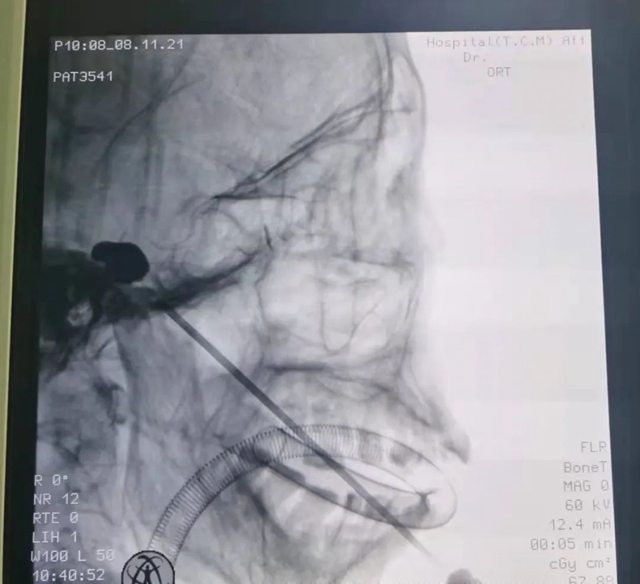

刘庆教授接诊后诊断为“三叉神经痛”,评估夏婆婆整体情况后,刘庆教授决定为其实施三叉神经微球囊压迫术。

手术在C臂影像引导下,将微球囊精准置入三叉神经压迫3-5分钟取出球囊,手术结束。